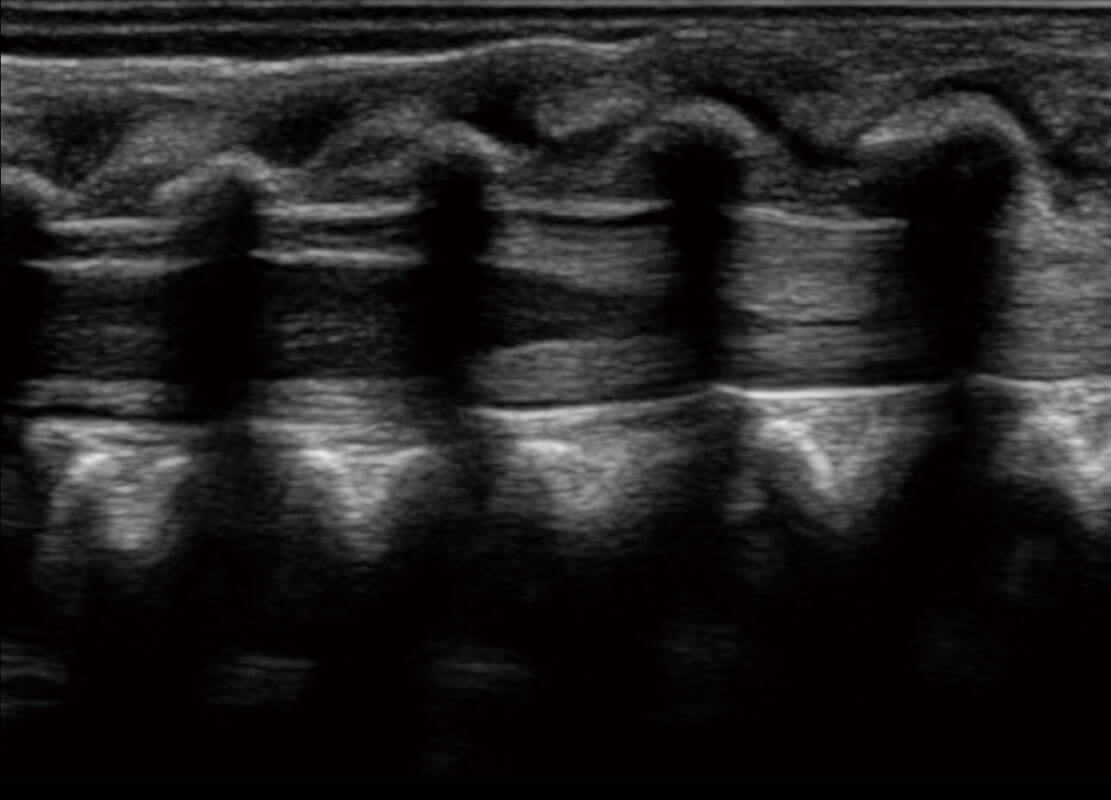

P60搭载宽频带线阵探头、宽景成像、弹性成像技术,为您提供乳腺应用方案。P60支持高频相控阵探头、线阵探头、腹部高频探头、腹部微凸探头等,丰富的探头群搭载敏感的彩色血流成像,适用于新生儿多种脏器检测要求,满足新生儿筛查需求。

新生儿脊髓圆锥

新生儿心脏